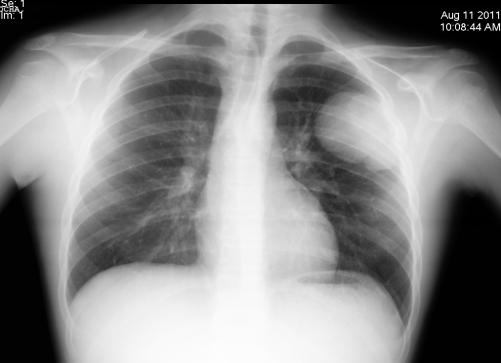

caso 1 Niño de 12 años en estudio por hallazgo anormal en una RX de tórax

caso 2 Niña de 2 años con disnea y anemia intensa

caso 3 Mujer de 40 años en seguimiento por tumor del estroma gastrointestinal (GIST)

solución